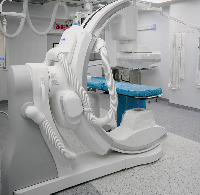

Выезд травматолога-ортопеда, рентгенолога Александра Валерьевича Дидковского.

На рабочем месте производится обучение работе на Вашем оборудовании.

Любого доктора можно быстро подготовить как рентгенлаборанта и дать необходимые знания для оценки рентгенограмм.

Изучение проблемы низкого качества рентгенограмм на Вашем оборудовании.